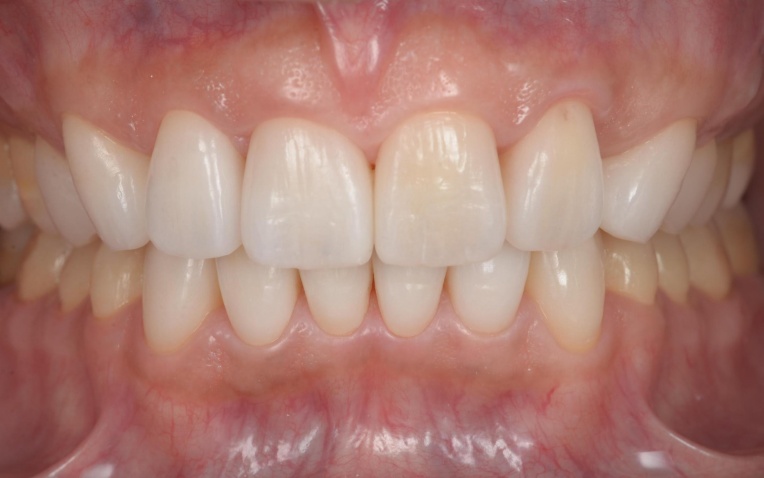

顎の位置が改善し、噛み合わせが安定したことを確認したあと、装着していた仮歯を除去してセラミックの被せ物に置き換えました。

最後に噛み合わせや見た目に問題がないかをしっかりとチェックして、治療を終了しています。

治療後